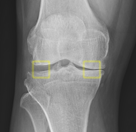

Knee Patella Malalignment

Knee Patella Malalignment AI

Automatic Diagnosis on X-ray. Measurement of Install-Salvati, Caton-Deschamps.

Aryan Kaul, Jason Pai, et al.